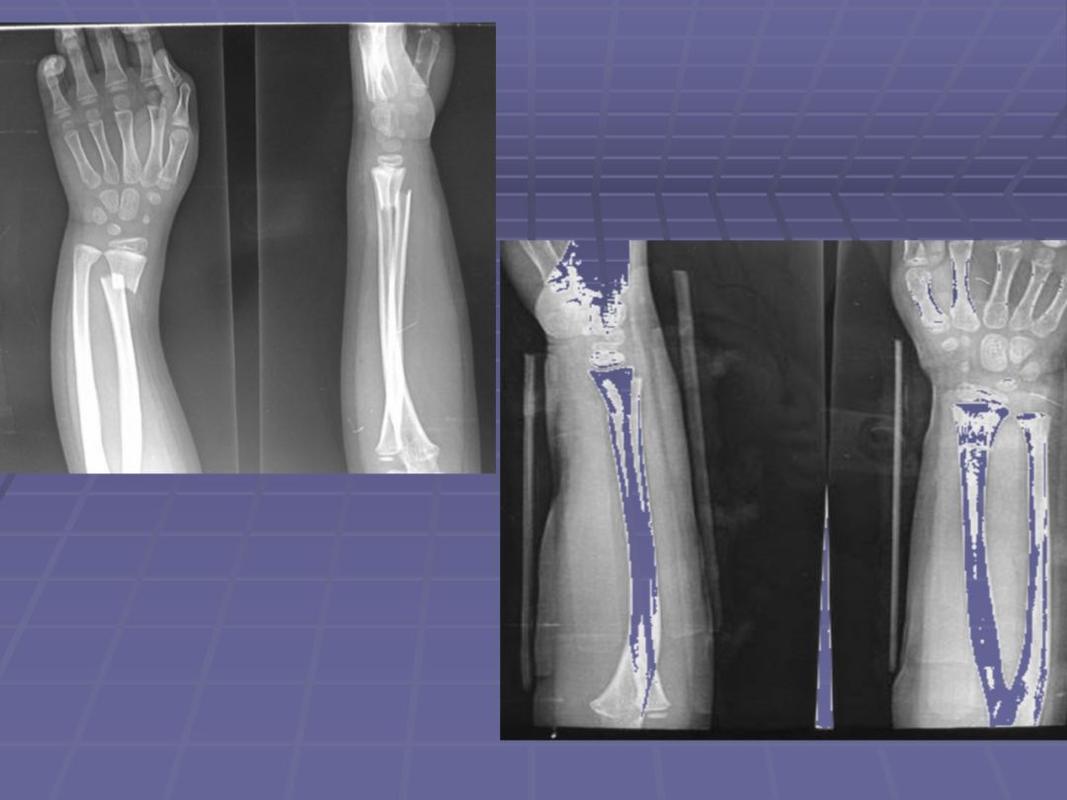

(四)2020-06,儿童尺桡骨远端骨折 经手法整复,小夹板固定.